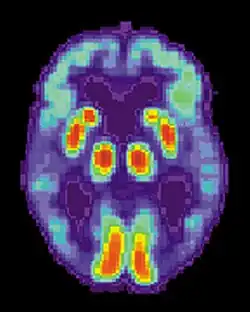

Positron emission tomography (PET) figure 4

PET scans use nuclear imaging to trace the presence a particular radioactive glucose or sugar. Glucose is the main fuel of the brain (Harris et al., 2018). Essentially, the sugar is injected into the body via a vein in a very small amount, and the PET scanner is able to see which areas of the brain are using the glucose up. The scanner uses this information to create a 3D image of the area being scanned, in this case the brain. This change in metabolic process is what allows the researchers using the PET scanner to determine the most active areas of the brain. This is not always a preferred method due to the use of radioactive material. Even though it is small, researches may need to perform multiple scans, and radiation can build up over time (Harris et al., 2018).